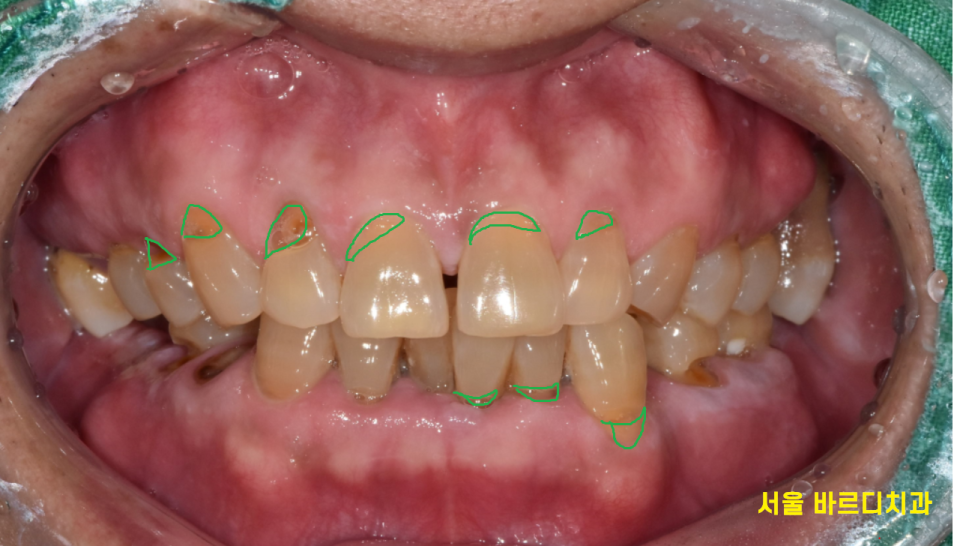

어금니가 몇 개 없어요

23.01.30

망월동 치과를 찾아오셨을 때

어금니 빠짐 부분만 5개였습니다~!

그러다 보니 씹을 수 있는 치아가

몇 개 없었습니다.

치아는 있어도 문제가 있는 부분도 많았는데요.

치석이 많아 잇몸 관리부터 필요했으니까요.

그동안 방치를 하셨다 하셨는데

앞니랑 군데군데 흔들리는 곳도 많았습니다.

치아가 패인 곳들을 때우고